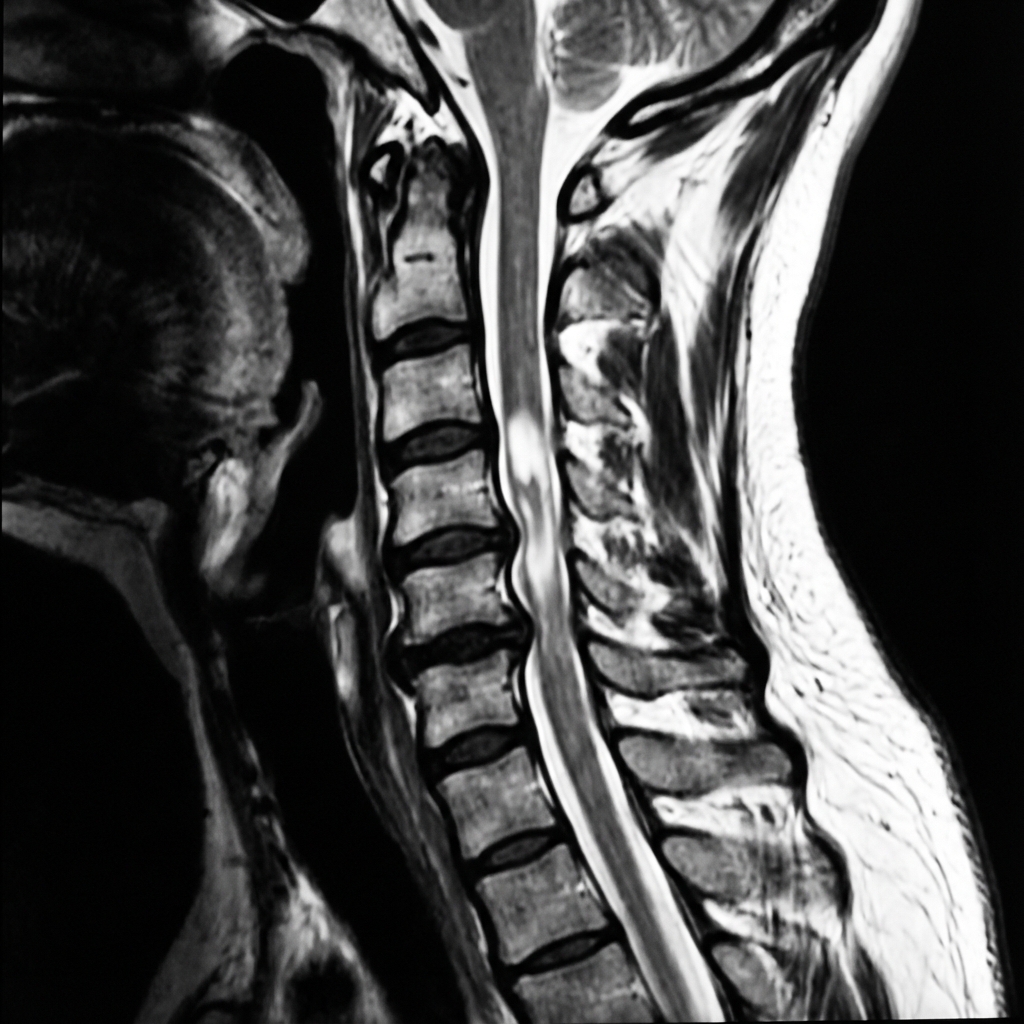

Sagittal T2-weighted MRI demonstrating multilevel cervical spondylosis with stenosis from C3-6. There is central cord T2 hyperintensity at C4-5 level indicating cord edema/contusion. There is no fracture or dislocation. This represents central cord syndrome from hyperextension injury in a patient with pre-existing cervical stenosis.